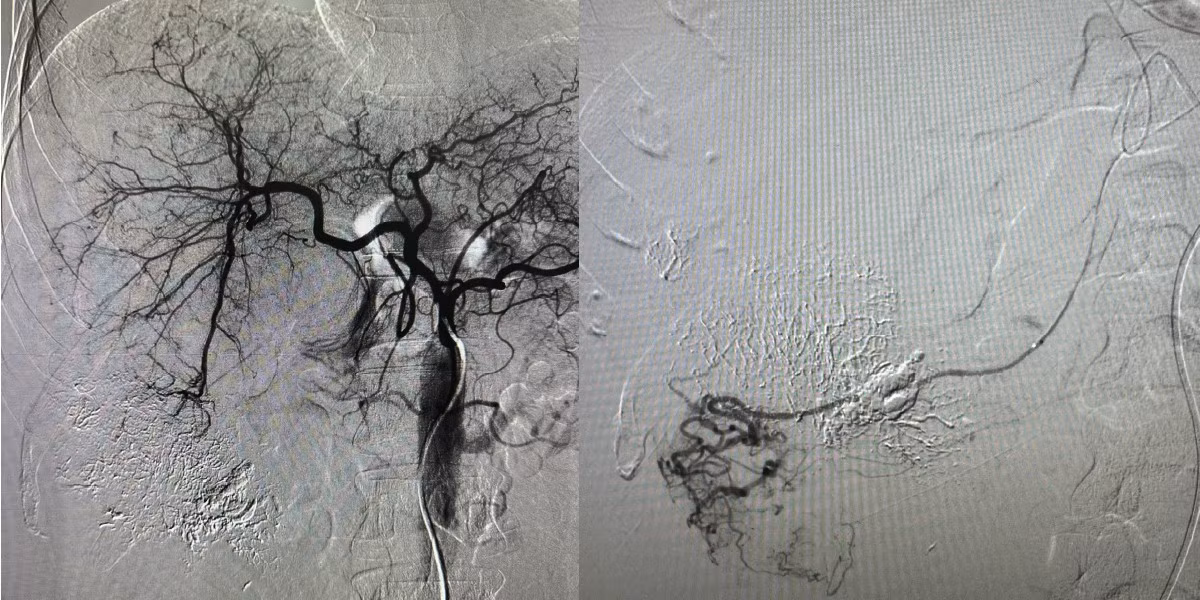

u-gan-vo-1.jpg

Nút mạch cho bệnh nhân u gan vỡ - Ảnh BVCC

Kỹ thuật nút mạch gan được thực hiện nhằm cầm máu tổn thương gan qua đường mạch máu mà không cần phẫu thuật mở. Đây là phương pháp ít xâm lấn, giúp kiểm soát tình trạng chảy máu hiệu quả và hạn chế tối đa nguy cơ biến chứng trong giai đoạn cấp tính.

Sau khi tiếp nhận, bệnh nhân nhanh chóng được hội chẩn đa chuyên khoa gồm chẩn đoán hình ảnh, ung bướu và hồi sức cấp cứu. Quyết định can thiệp nút mạch gan được đưa ra sau khi đánh giá tình trạng mất máu trong ổ bụng và tổn thương tại khối u.